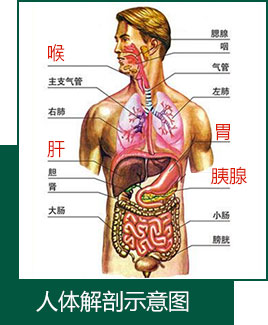

酗酒的人寿命比正常人平

均,缩短10-20年。全国约9万

人因过量饮酒住院,其中2.5

万人死亡。多因饮酒引起的肝

硬化、胃癌、缺血性心脏病等

疾病引起。